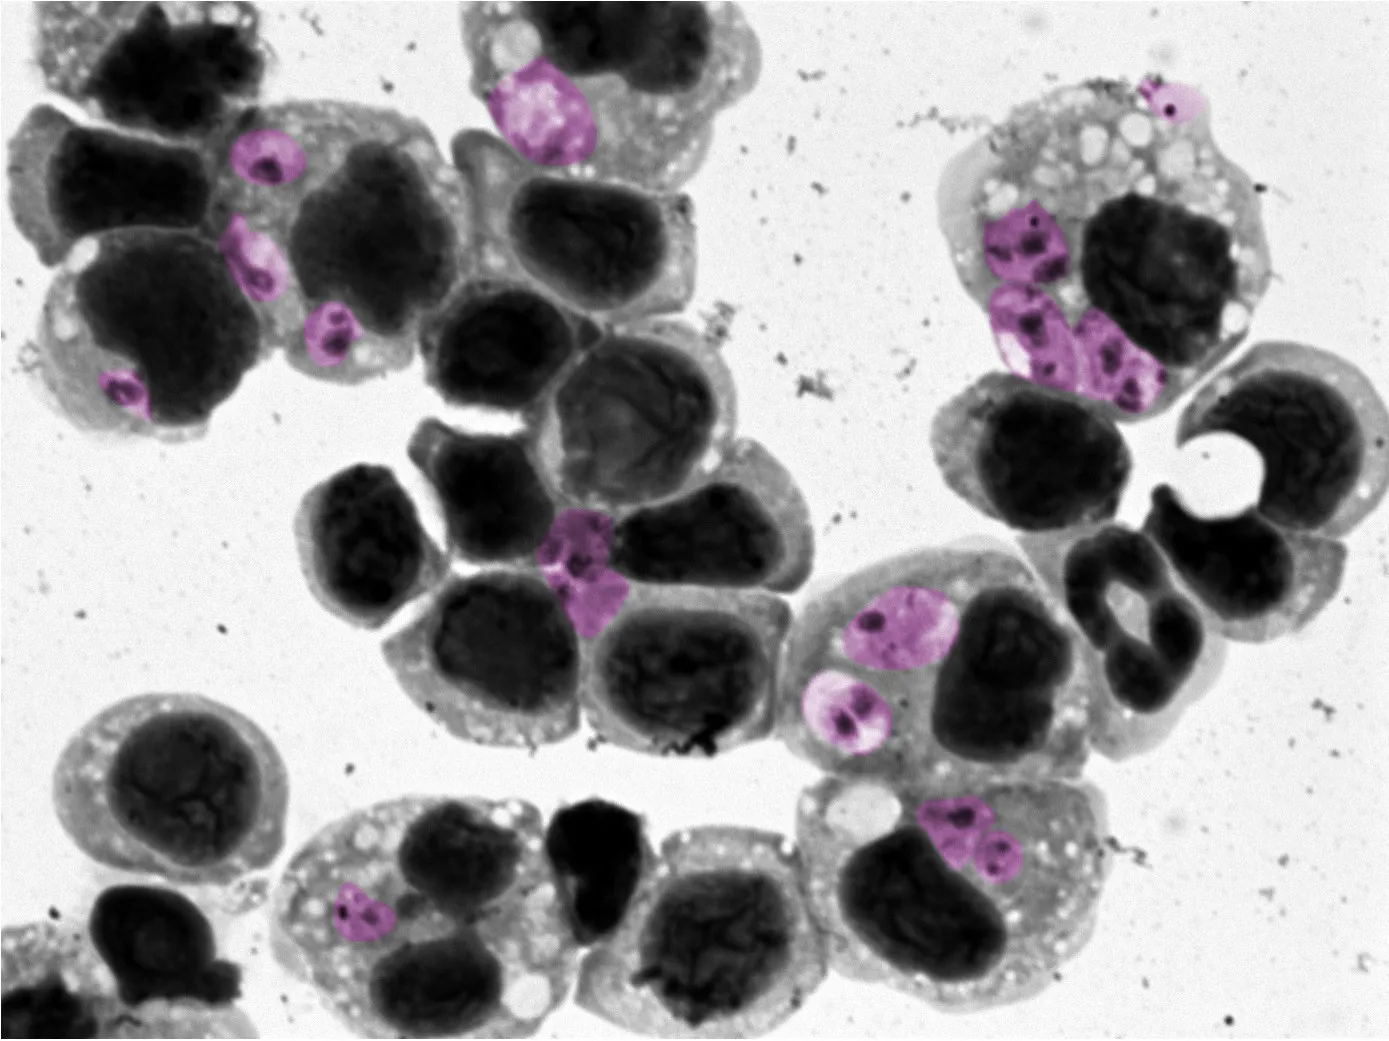

$3M NIH Grant Supports Genomic Approach to Curing ‘Neglected’ Disease

Najib El-Sayed is leading a team that is using powerful sequencing tools to combat a painful, disfiguring parasitic skin condition.

UMD Researchers Discover Way to Predict Treatment Success for Parasitic Skin Disease

Findings from a new study co-authored by Najib El-Sayed could help doctors select more effective treatments earlier for patients suffering from leishmaniasis.